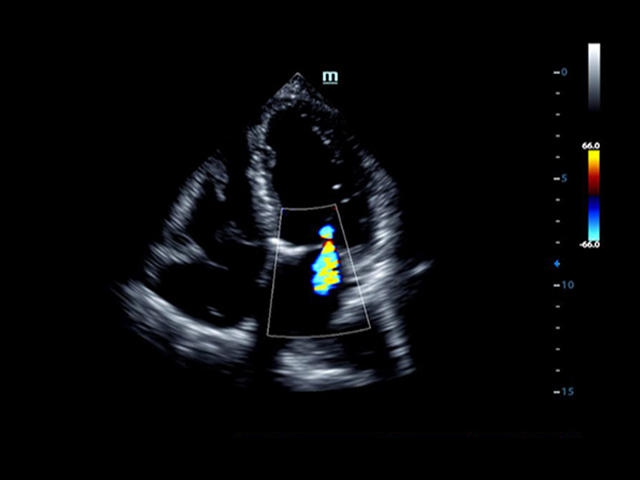

• LVO - опция проведения исследования левого желудочка сердца с применением контрастных веществ;

• LVO - опция проведения исследования левого желудочка с применением контрастных веществ

• TDI (Tissue Doppler imaging, including TDI Color, Power, PW and M mode) - пакет тканевой допплерографии, включая цветное картирование, импульсный тканевой допплер, энергетический тканевой допплер и тканевой М-режим